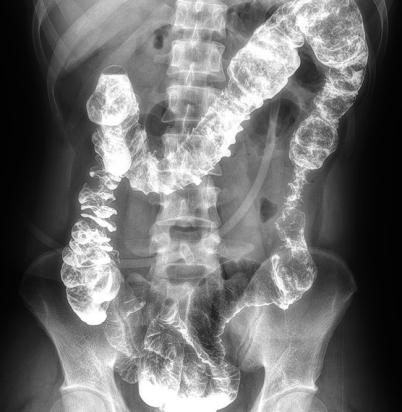

多功能動態(tài)平板DR,采用U型臂結構,具有靜態(tài)DR攝影、數(shù)字透視、數(shù)字造影和可視化攝影的功能。

● 可快速選擇、預設所需要的視野,節(jié)約擺位時間;

● 根據(jù)拍攝需求或技師使用習慣一鍵切換光束范圍;

● 可根據(jù)不同的體位協(xié)議,自動調整光束大小。